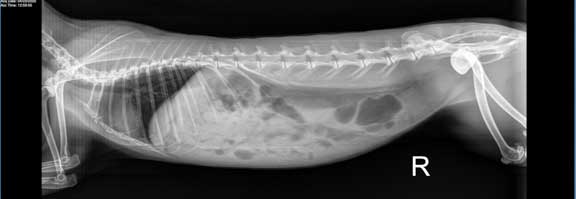

It never hurts to be thorough during this pre-anesthetic exam and take a radiograph (X-ray). The following 3 radiographs, on rabbits that were seemingly normal, show why.

This one has a solitary urinary bladder stone in the top right of the radiograph.